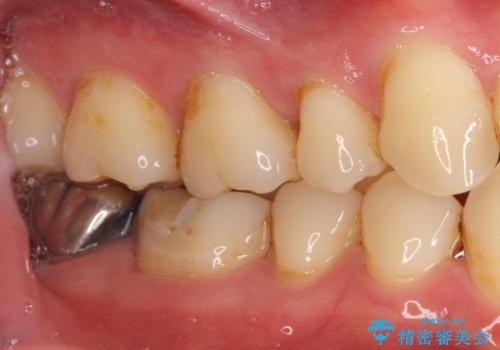

- 奥歯の違和感を主訴に来院された患者様です。

銀歯を除去し、歯周外科処置(右下7遠心の骨整形及びディスタルウェッジ)を行った後にメタルボンドクラウンによる補綴を行いました。

不適合な銀の詰め物とう蝕の除去により奥歯の違和感がなくなり、セラミック治療により機能性・審美性が向上し、患者様に喜んで頂けました。